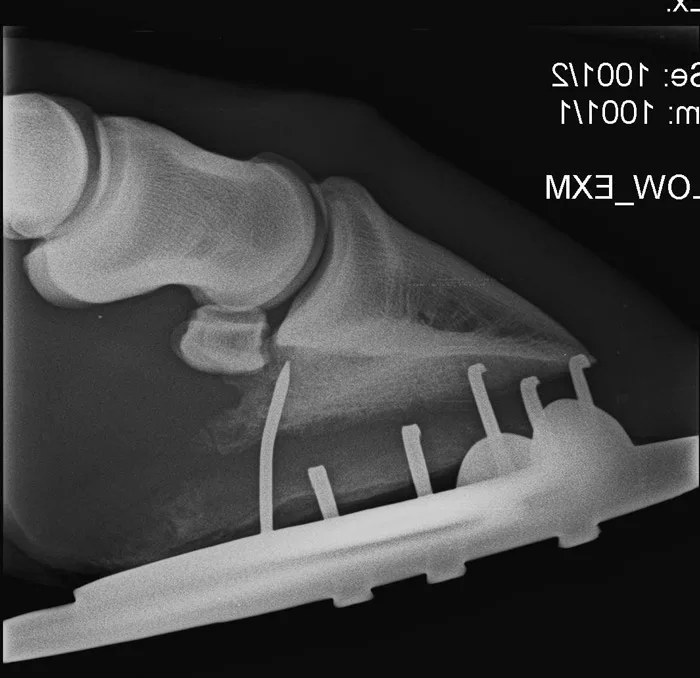

Stressing the need for each side to work together, two of these presentations addressed how radiographs and magnetic resonance imaging (MRI) can help diagnose, but also provide better direction for the farrier counterparts with their role in helping the horse.

Although an infrequent occurrence for the typical farrier, Weller holds that providing radiographs more frequently to the farrier would be a smart investment.

Of course, farriery management is only one reason for radiographing the foot. If lameness is localized to the foot, pre-purchase exams and penetrating wounds are other common needs for capturing foot or distal limb radiographs. Measuring the frequency of use in the clinical setting of her vet school, Weller says that farriery comes in second for frequency of use only behind lameness localized to the foot.